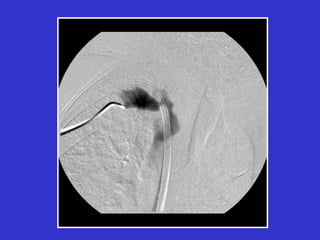

Angioplasty Procedure

Diagnostic fistulogram

access

vascular

sheath

position

angioplasty balloon

across stenosis

fully inflate

balloon

stenosis

Post-PTA